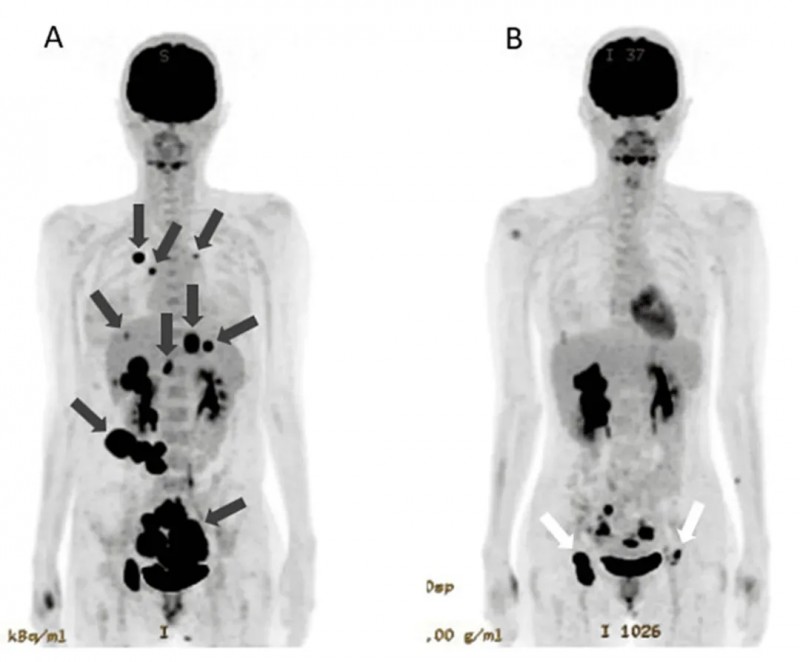

2、病灶显著改善:治疗前全身PET-CT提示双侧卵巢原发性病灶,同时合并腹膜、肝脏、骨骼、肺部等广泛转移;治疗第142天复查,原发性肿瘤明显缩小,肺转移灶及腹膜播散灶完全消失,肝转移灶显著缩小(详见下图),患者已计划进行原发肿瘤根治性切除术。

▲图源“Cureus”,版权归原作者所有,如无意中侵犯了知识产权,请联系我们删除